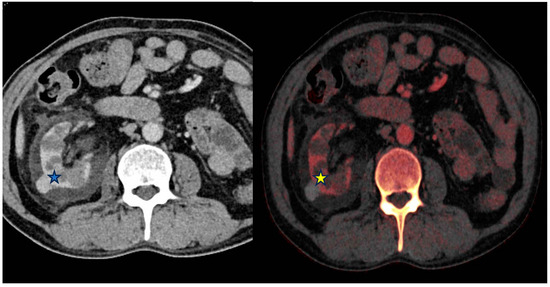

5.1. Examples in the Gastrointestinal System

5.1.1. Bowel

5.1.2. Appendix